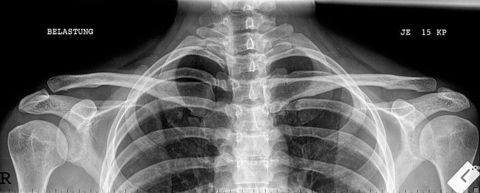

| AC Joints | ANATOMY: Bilateral AC joints included and open CRITERIA: non weight bearing and weight bearing projections marked correctly both joints included lateral clavicle almost horizontal POSITIONING: CR perpendicular @ jugular notch |